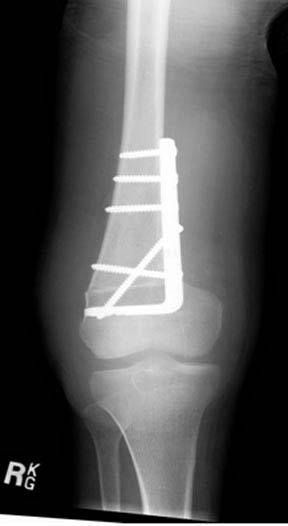

2.This final radiograph demonstrates the profound correction of the deformity. The osteotomy takes approximately eight weeks to heal. The patient is kept on crutches throughout this period of time.